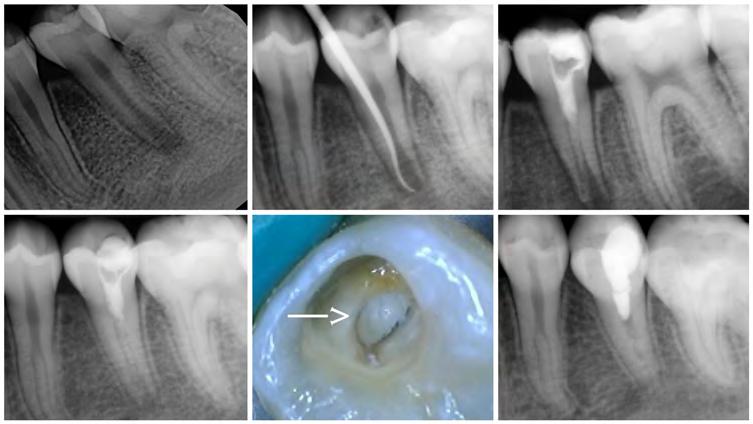

Case 1: Modified Regeneration (Figure 1)

A 12-year-old girl presented with her mom with a chief complaint of pain and swelling of the lower left mandibular vestibule. Radiographic imaging revealed a periapical radiolucency (PARL) associated with tooth #20, which had an incompletely formed blunderbuss apex. No caries or restorations were noted, but the tooth was very painful to the touch and did not respond to vitality testing. A diagnosis of pulp necrosis with acute apical access was made.

The likely cause of the necrotic pulp was a worn-down dens evaginatus. The recommended treatment was root canal therapy, more specifically, apexification. After access preparation, bloody and purulent discharge was noted. To obtain working length, a large size 80k-file was placed in the canal to an estimated length and a radiograph taken.

The canal was irrigated with 3 ml of 5.25% sodium hypochlorite. The EndoActivator (Dentsply, Tulsa, OK) was used to sonically agitate the irrigant in the canal to ensure thorough disinfection. Light instrumentation with both rotaries and hand files was completed. The canal was dried with a surgical microsuction tip. CH (Ultracal XS, Ultradent Products Inc, South Jordan, UT) was used as an inter-visit medicament. The tooth was temporarily restored with intermediate restorative material (IRM).

The patient returned after four weeks for completion of treatment. She reported that all symptoms had subsided. Clinical examination revealed that the swelling had resolved. CH was removed from the canal with irrigation and activation with the EndoActivator. The canal was irrigated with a combination of 3 ml of 5.25% sodium hypochlorite and 3 ml of 17% EDTA (ethylene diamine tetra-acetic acid). The canal was dried with a surgical microsuction tip. Red, healthy-looking blood was noted in the apical third of the canal. EndoSequence BC putty (Brasseler USA, Savannah, GA) was used as the material of choice due to its biocompatibility. Care was taken to make sure it was placed 5 mm from the apex. Multiple radiographs were needed to confirm proper placement of the putty.

Once the BC putty was in place for 15 minutes, to allow it to set, the canal was etched, rinsed, dried, and a dual-cure composite placed deep into the canal and allowed to selfcure for about five minutes. The access opening was restored with regular composite (Dentsply Sirona, Charlotte, NC), and the patient was put on a recall schedule to monitor healing.

At the one-year recall visit, the patient was completely asymptomatic, and radiographic examination revealed almost complete healing of the periapical radiolucency. A significant increase in root length and thickness was noted.